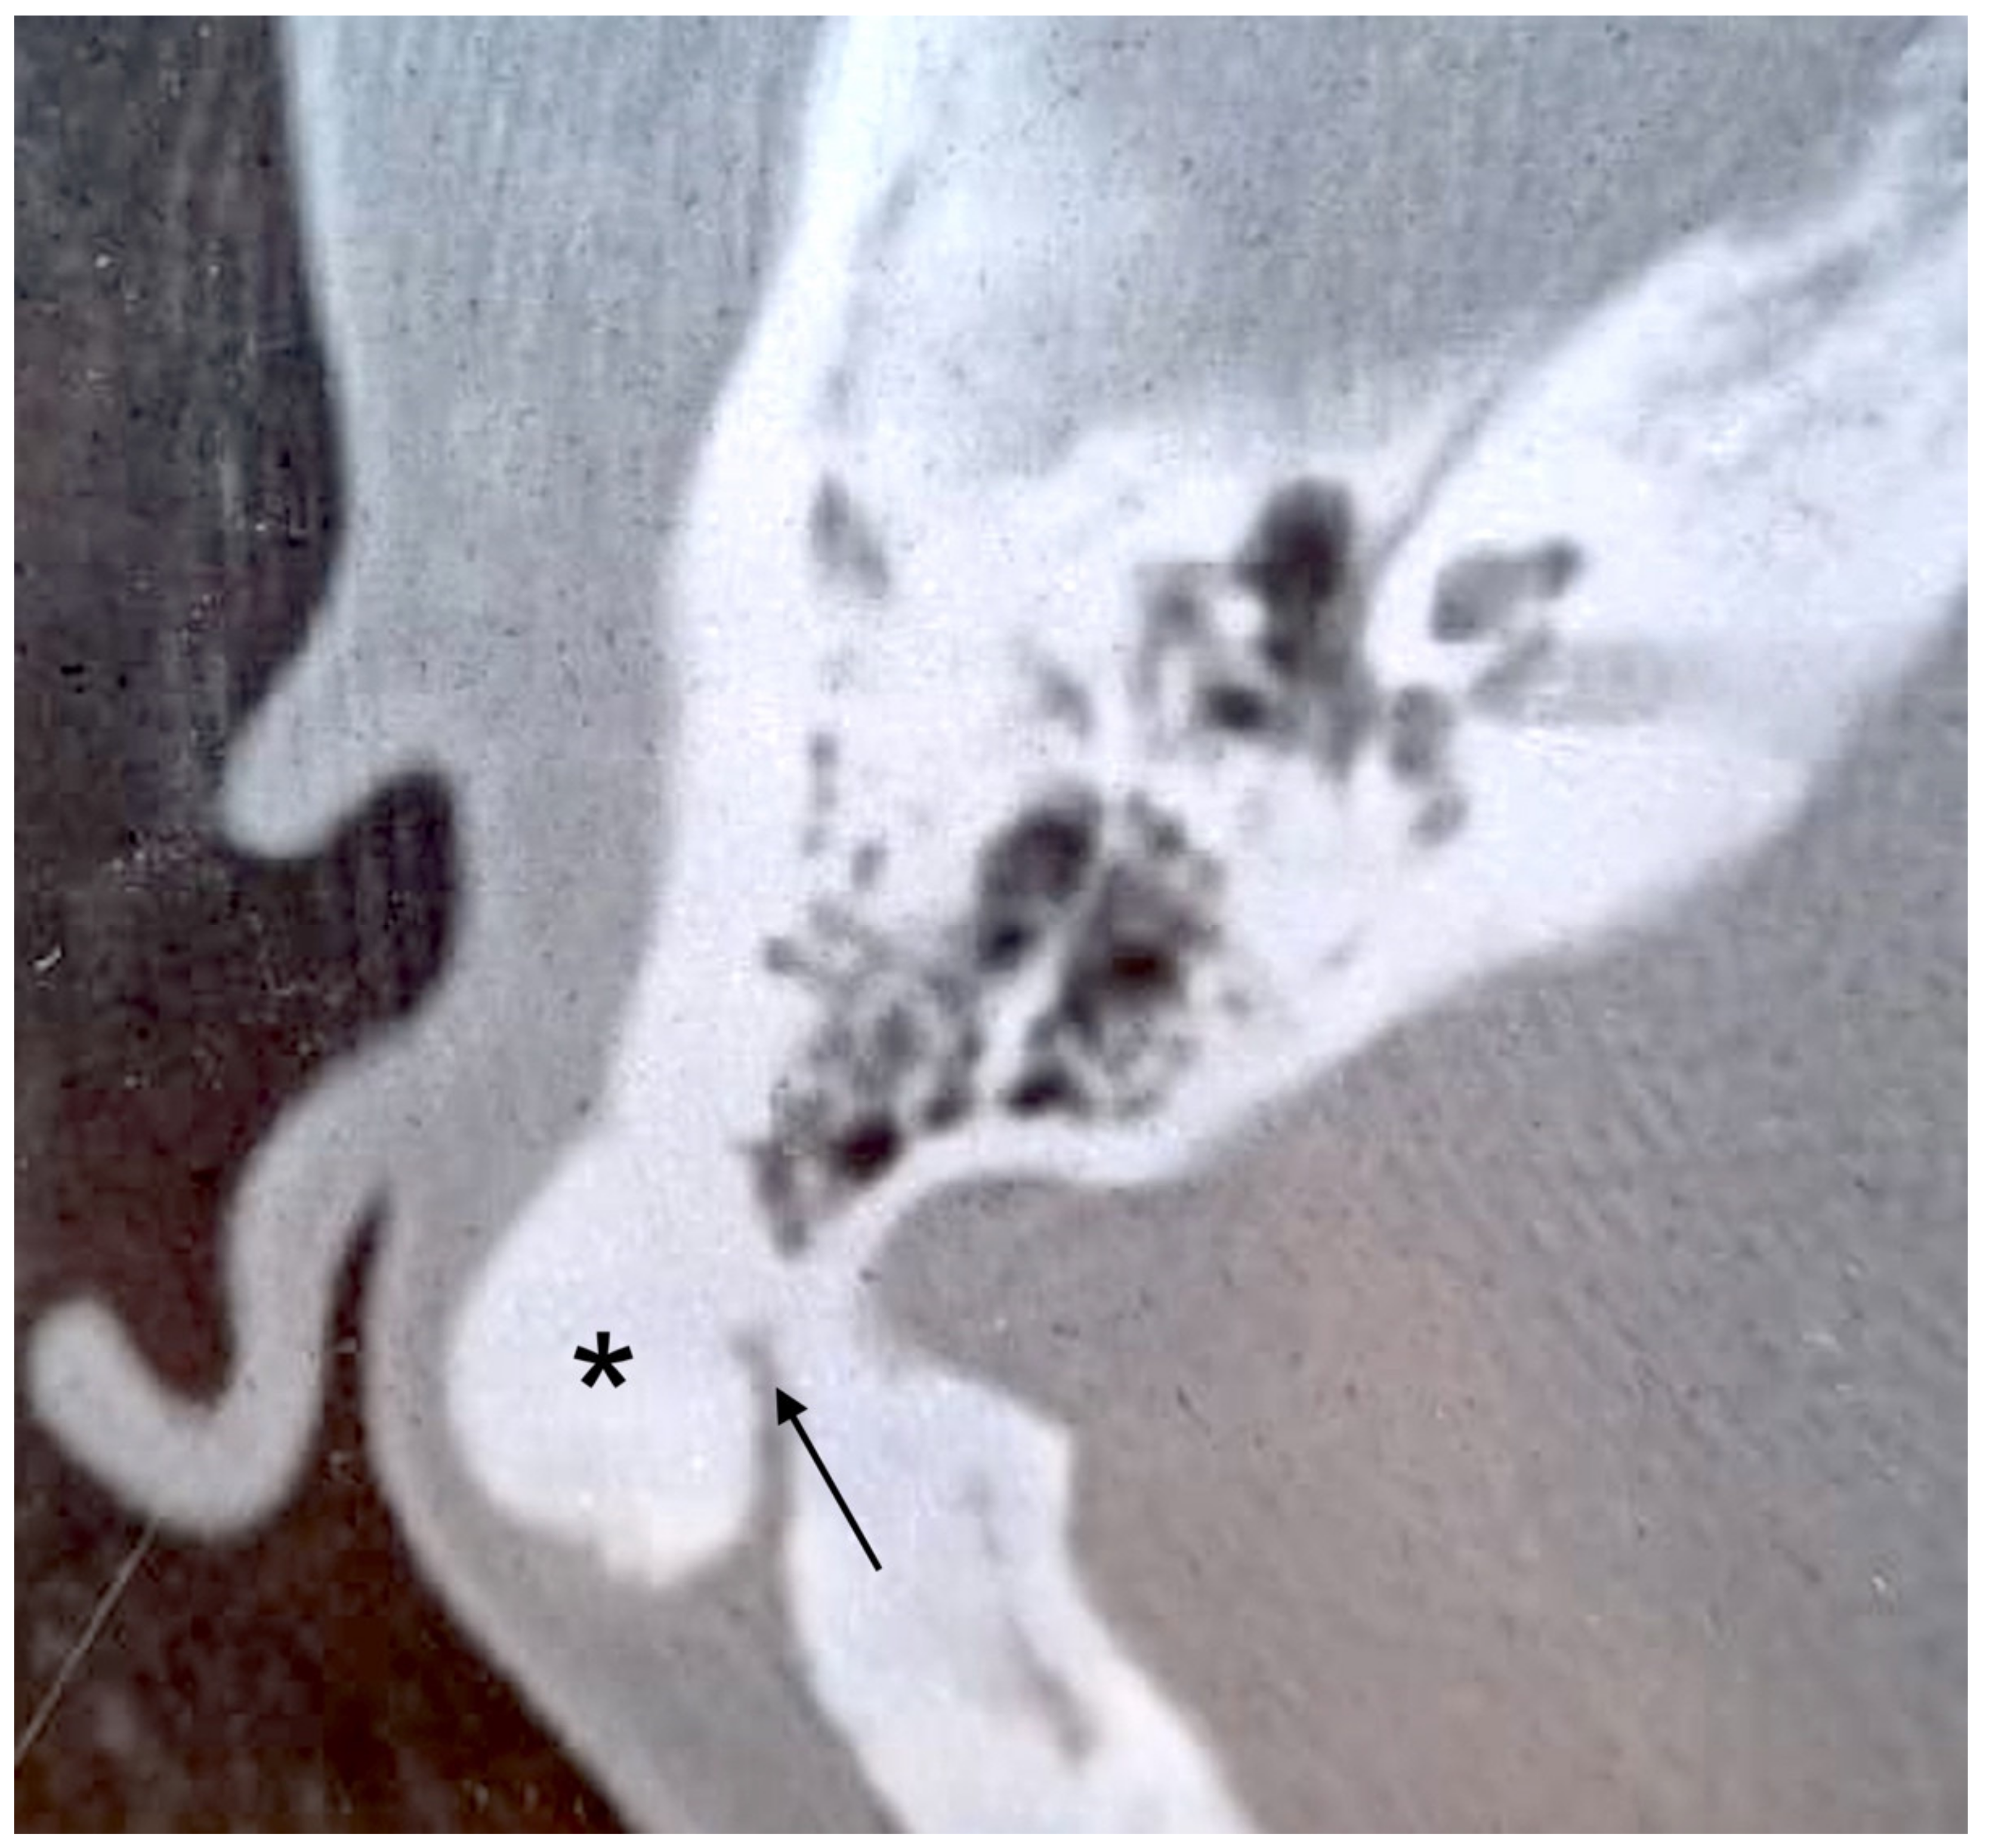

3.1. Case 1